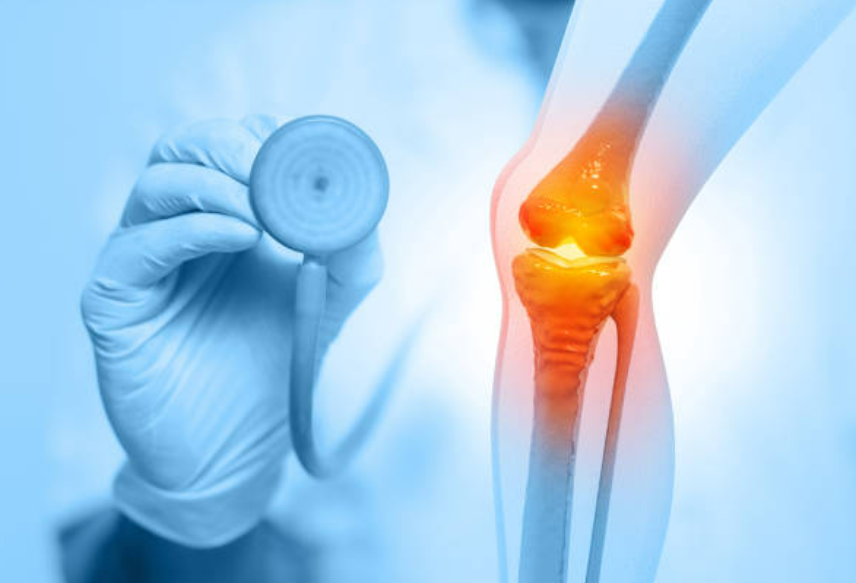

관절염이란 무엇인가

관절염은 관절에 염증이 생기는 만성적인 질환입니다. 주로 류마티스 관절염과 퇴행성 관절염으로 나뉘며, 이들은 다른 원인과 증상을 가지고 있습니다. 관절염은 주로 연령에 따라 발생하는데, 중년 이후에 더 흔하게 발생합니다. 이러한 질환은 관절의 기능을 제한하고 일상생활에 불편을 초래할 수 있습니다.

류마티스 관절염은 자체 면역 시스템이 관절을 공격함으로써 발생합니다. 면역 시스템의 과도한 반응은 관절염의 주요 원인으로 작용하며, 이로 인해 관절의 염증과 통증이 발생합니다. 퇴행성 관절염은 연령과 노화에 따라 발생하는데, 연령에 비례하여 연골의 퇴화가 진행됩니다. 이러한 연골의 퇴화는 관절의 마찰, 염증 및 통증을 초래합니다.